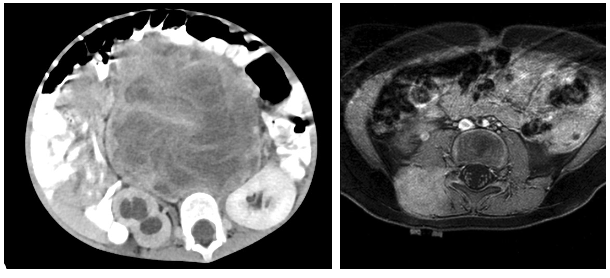

• 영상검사: CT/MRI, 흉부CT (폐전이 확인), 뼈 스캔/PET CT

좌: retroperitoneal rhabdomyosarcoma

우: paraspinal rhabdomyosarcoma